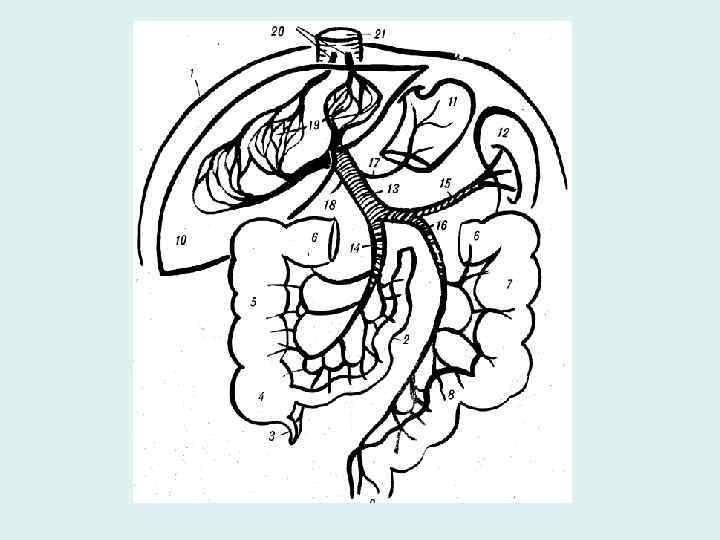

Воротная вена • Собирает кровь от непарных органов брюшной полости • Истоки (корни): селезеночная вена, верхняя и нижняя брыжеечные вены • Притоки: желудочные правая и левая, препилорическая, околопупочные вены

Воротная вена